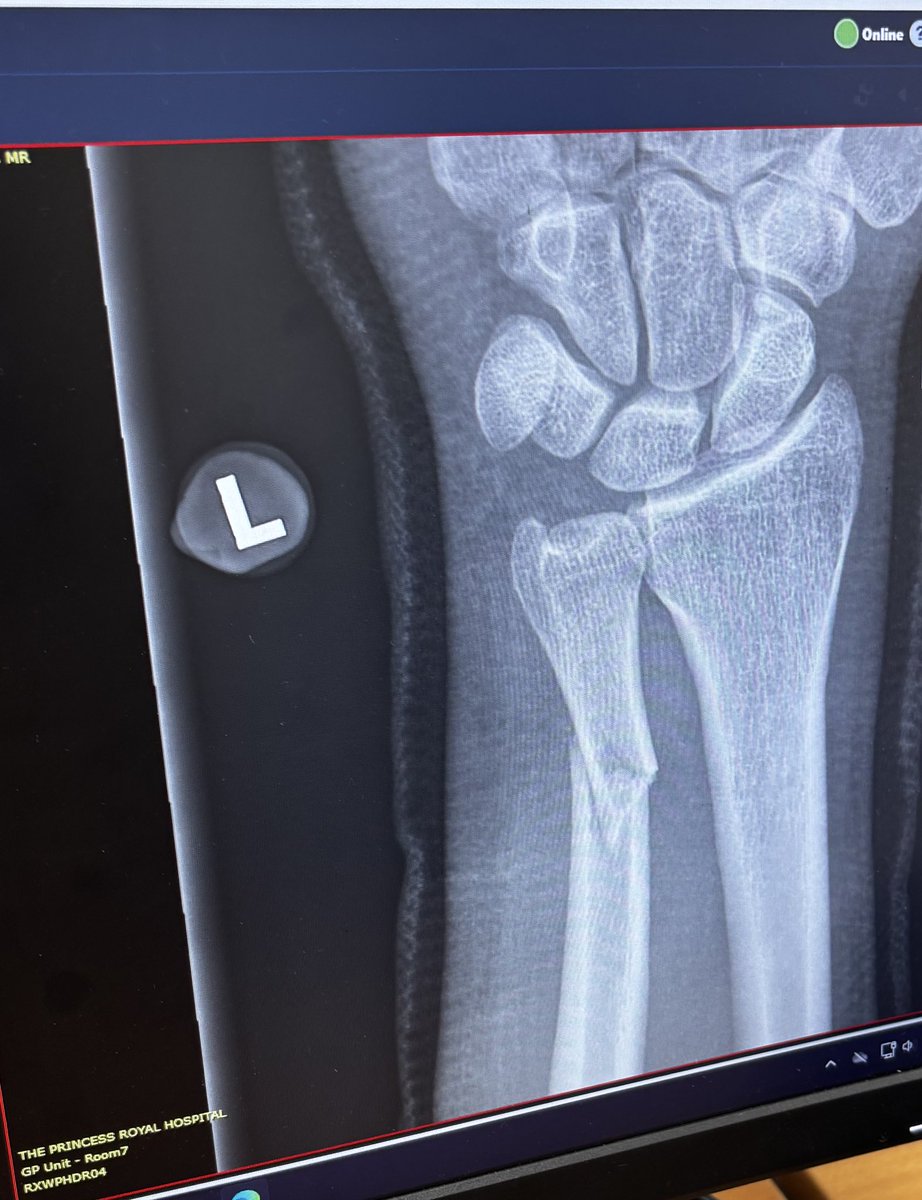

THANK YOU: We're hugely appreciative of the PA message from @chorleyfc, wishing @Brandon27Hall a speedy recovery from his fractured wrist. Thank you on Brandon's behalf, you Magpies! 🙏🏼